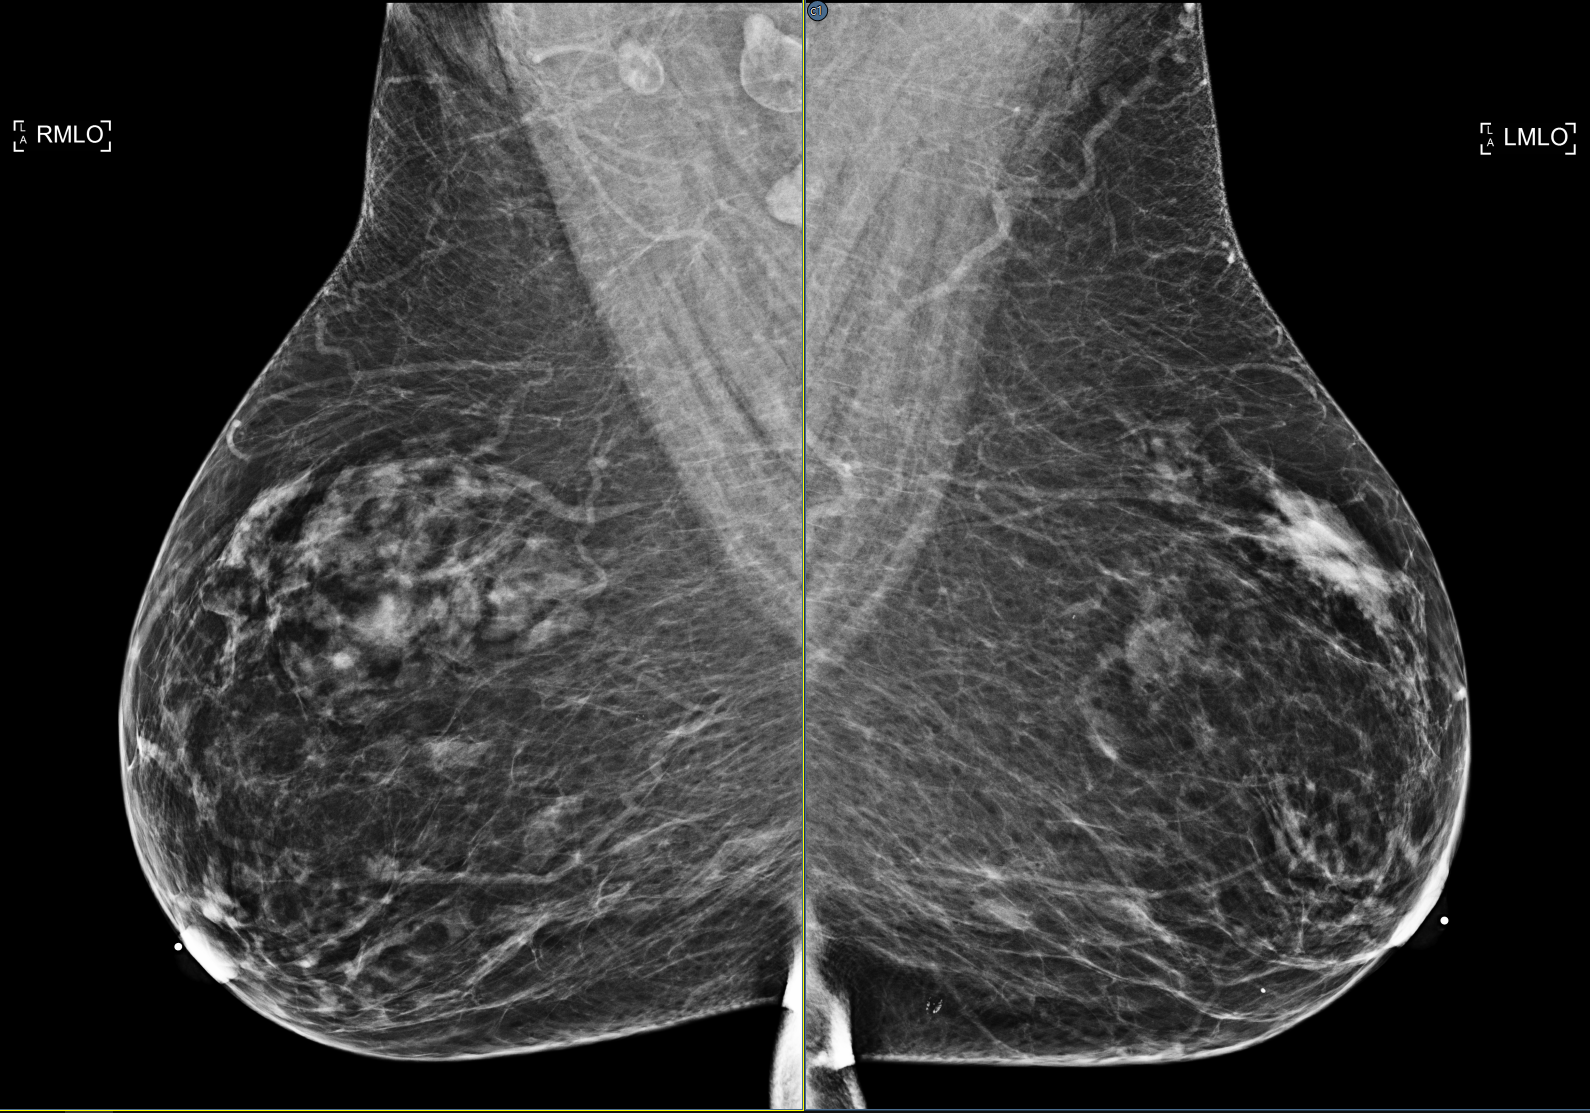

Improving skin line detection

The skin line detection algorithm uses parameters meant to accommodate most MG images. When exceptions exist, the user can modify the algorithm’s parameters to see if the processing can complete successfully. These parameters are in the configuration panel on the Images/Mammography View page. They include Skin line detection margin, the margin used to start the detection, Number of Thresholds, defining the number of custom thresholds, and Custom thresholds, to override an invalid calculated threshold.

Cross reference GE tomo CAD findings onto 2D images

The viewer applies the Deephealth SaigeDx AI results (algorithm 3.1.0 and later) to images acquired by a General Electric Pristina mammography system.